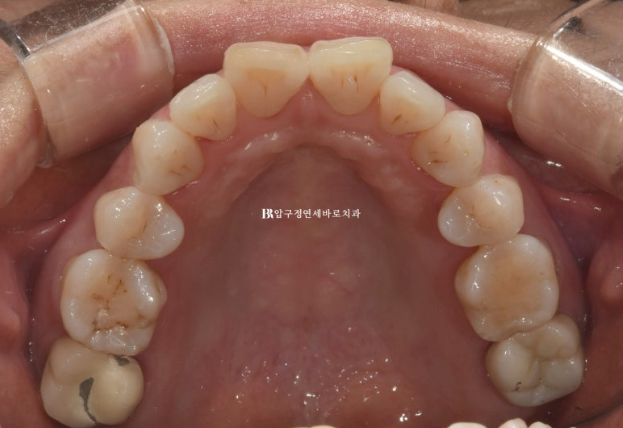

위 앞니 두개가 튀어나와있고 회전이 되어있습니다.

정식용어는 아니지만 이런 치아를 나비치아 라고 합니다.

배열이 가지런해졌고 소량의 치간삭제를 통해 블랙트라이앵글도 줄었습니다.

단 위 앞니 높낮이 단차가 있어서 이 부분을 추가장치에서 해결하기로 했습니다.

뻗친 앞니 각도가 개선이 되고 나비치아 토끼이가 배열이 되었습니다.